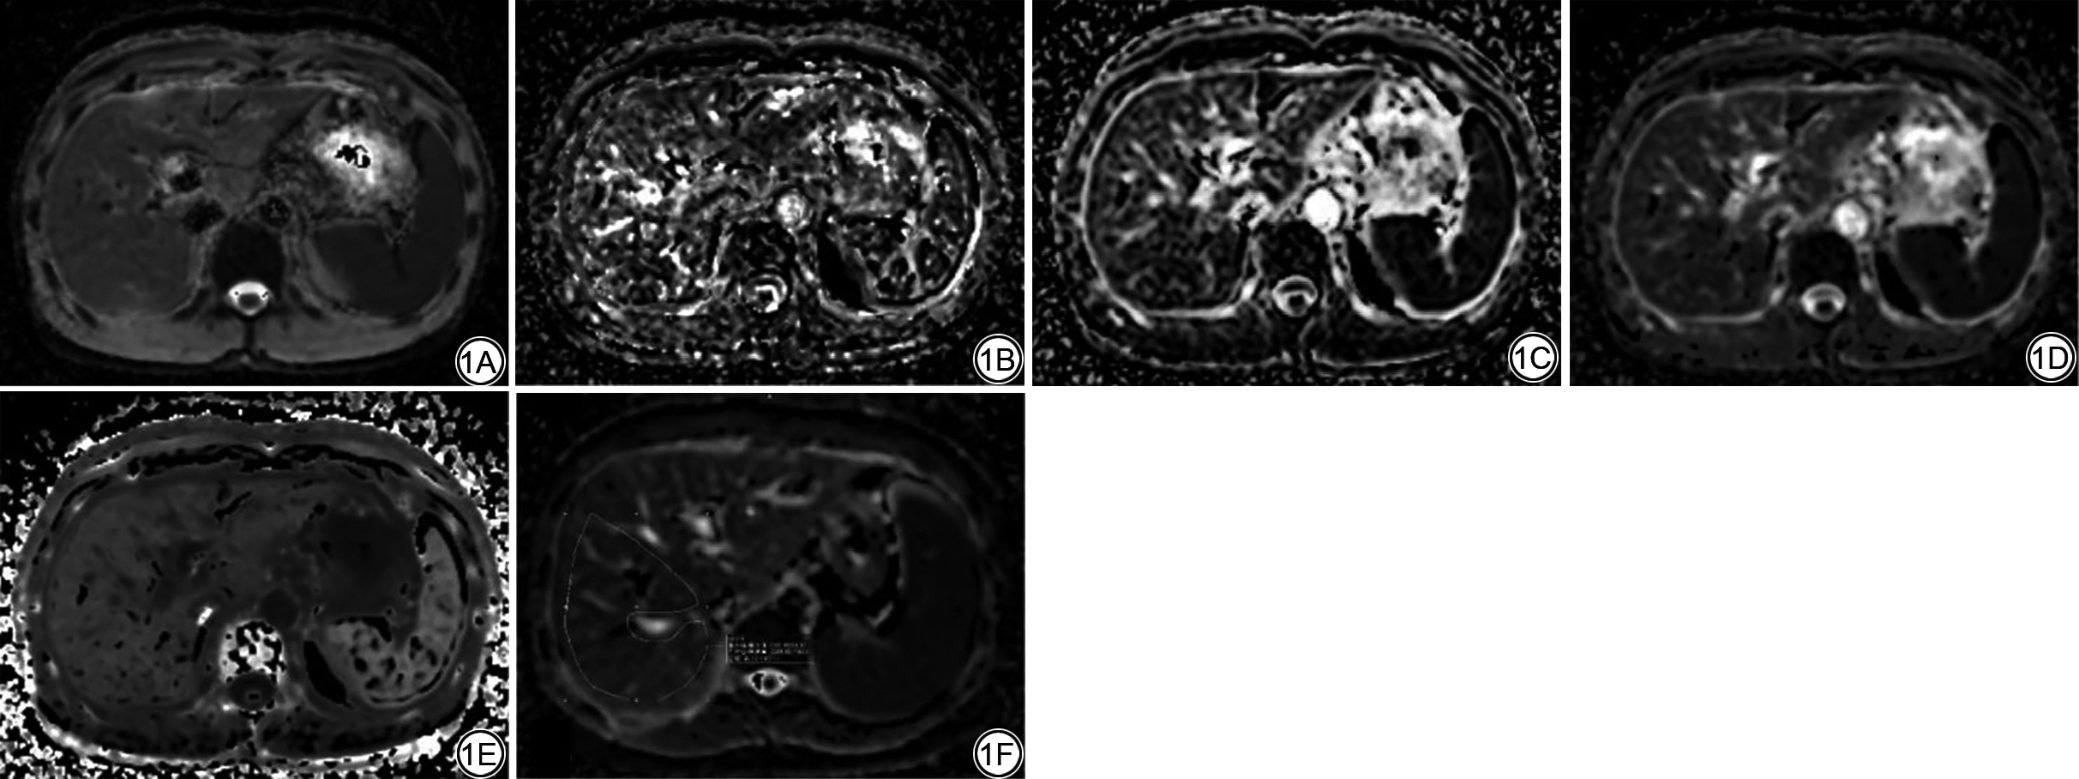

由2名经验丰富且不知晓患者临床信息的MRI诊断医师(分别为13年工作经验的副主任医师和7年工作经验的主治医师)进行数据的采集、处理及分析。IVIM模型计算生成单纯扩散系数(true diffusion coefficient, D)图,微循环灌注系数(pseudo-diffusion coefficient, D*)图和灌注分数(perfusion fraction, f)图。DKI模型计算生成平均扩散系数(apparent diffusivity, MD)图,扩散峰度(excess kurtosis, MK)图。使用ITK-SNAP软件(3.8.0版,http://www.itksnap.org/)在肝右叶近肝门水平勾画ROI,同时避开大血管、胆管、病变和伪影区域。在一组参数图上选择ROI,并复制到其他参数图上。分别得到IVIM模型评价指标D,D*,f,以及DKI模型评价指标MD,MK。详见图1

图1  男,56 岁,慢性乙肝患者,肝纤维化S2 期。1A~1C:分别为IVIM参数D、D*、f 图;1D~1E:分别为DKI 参数MD、MK图;1F:ROI 勾画示意图。IVIM:体素内不相干运动;D:单纯扩散系数;D*:微循环灌注系数;f:灌注分数;DKI:扩散峰度成像;MD:平均扩散系数;MK:扩散峰度;ROI:感兴趣区。

Fig. 1  Male, 56 years old, patient with chronic hepatitis B, liver fibrosis stage S2. 1A-1C: IVIM parameter maps (D map, D* map, f map, respectively); 1D-1E: DKI parameter maps (MD map, MK map, respectively); 1F: Schematic diagram of ROI delineation. IVIM: intravoxel incoherent motion; D: true diffusion coefficient; D*: pseudo-diffusion coefficient; f: perfusion fraction; DKI: diffusion kurtosis imaging; MD: apparent diffusivity; MK: excess kurtosis; ROI: region of interest.